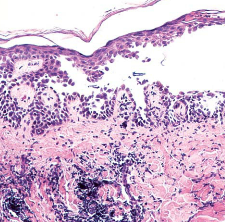

Darkly pigmented, variegated lesions distributed primarily on the trunk and non-sun-exposed skin. These moles feature a combination of architectural disorder (rete-to-rete bridging of melanocytes) and cytologic atypia (melanocytes with large atypical nuclei). These patients are at an increased risk of developing melanoma.

Dysplastic nevi

(image displays bridging of rete ridges and melanocytes with cytological atypia, curved arrows)